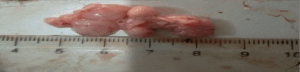

Figure 6. Haemorrhagic salpingitis